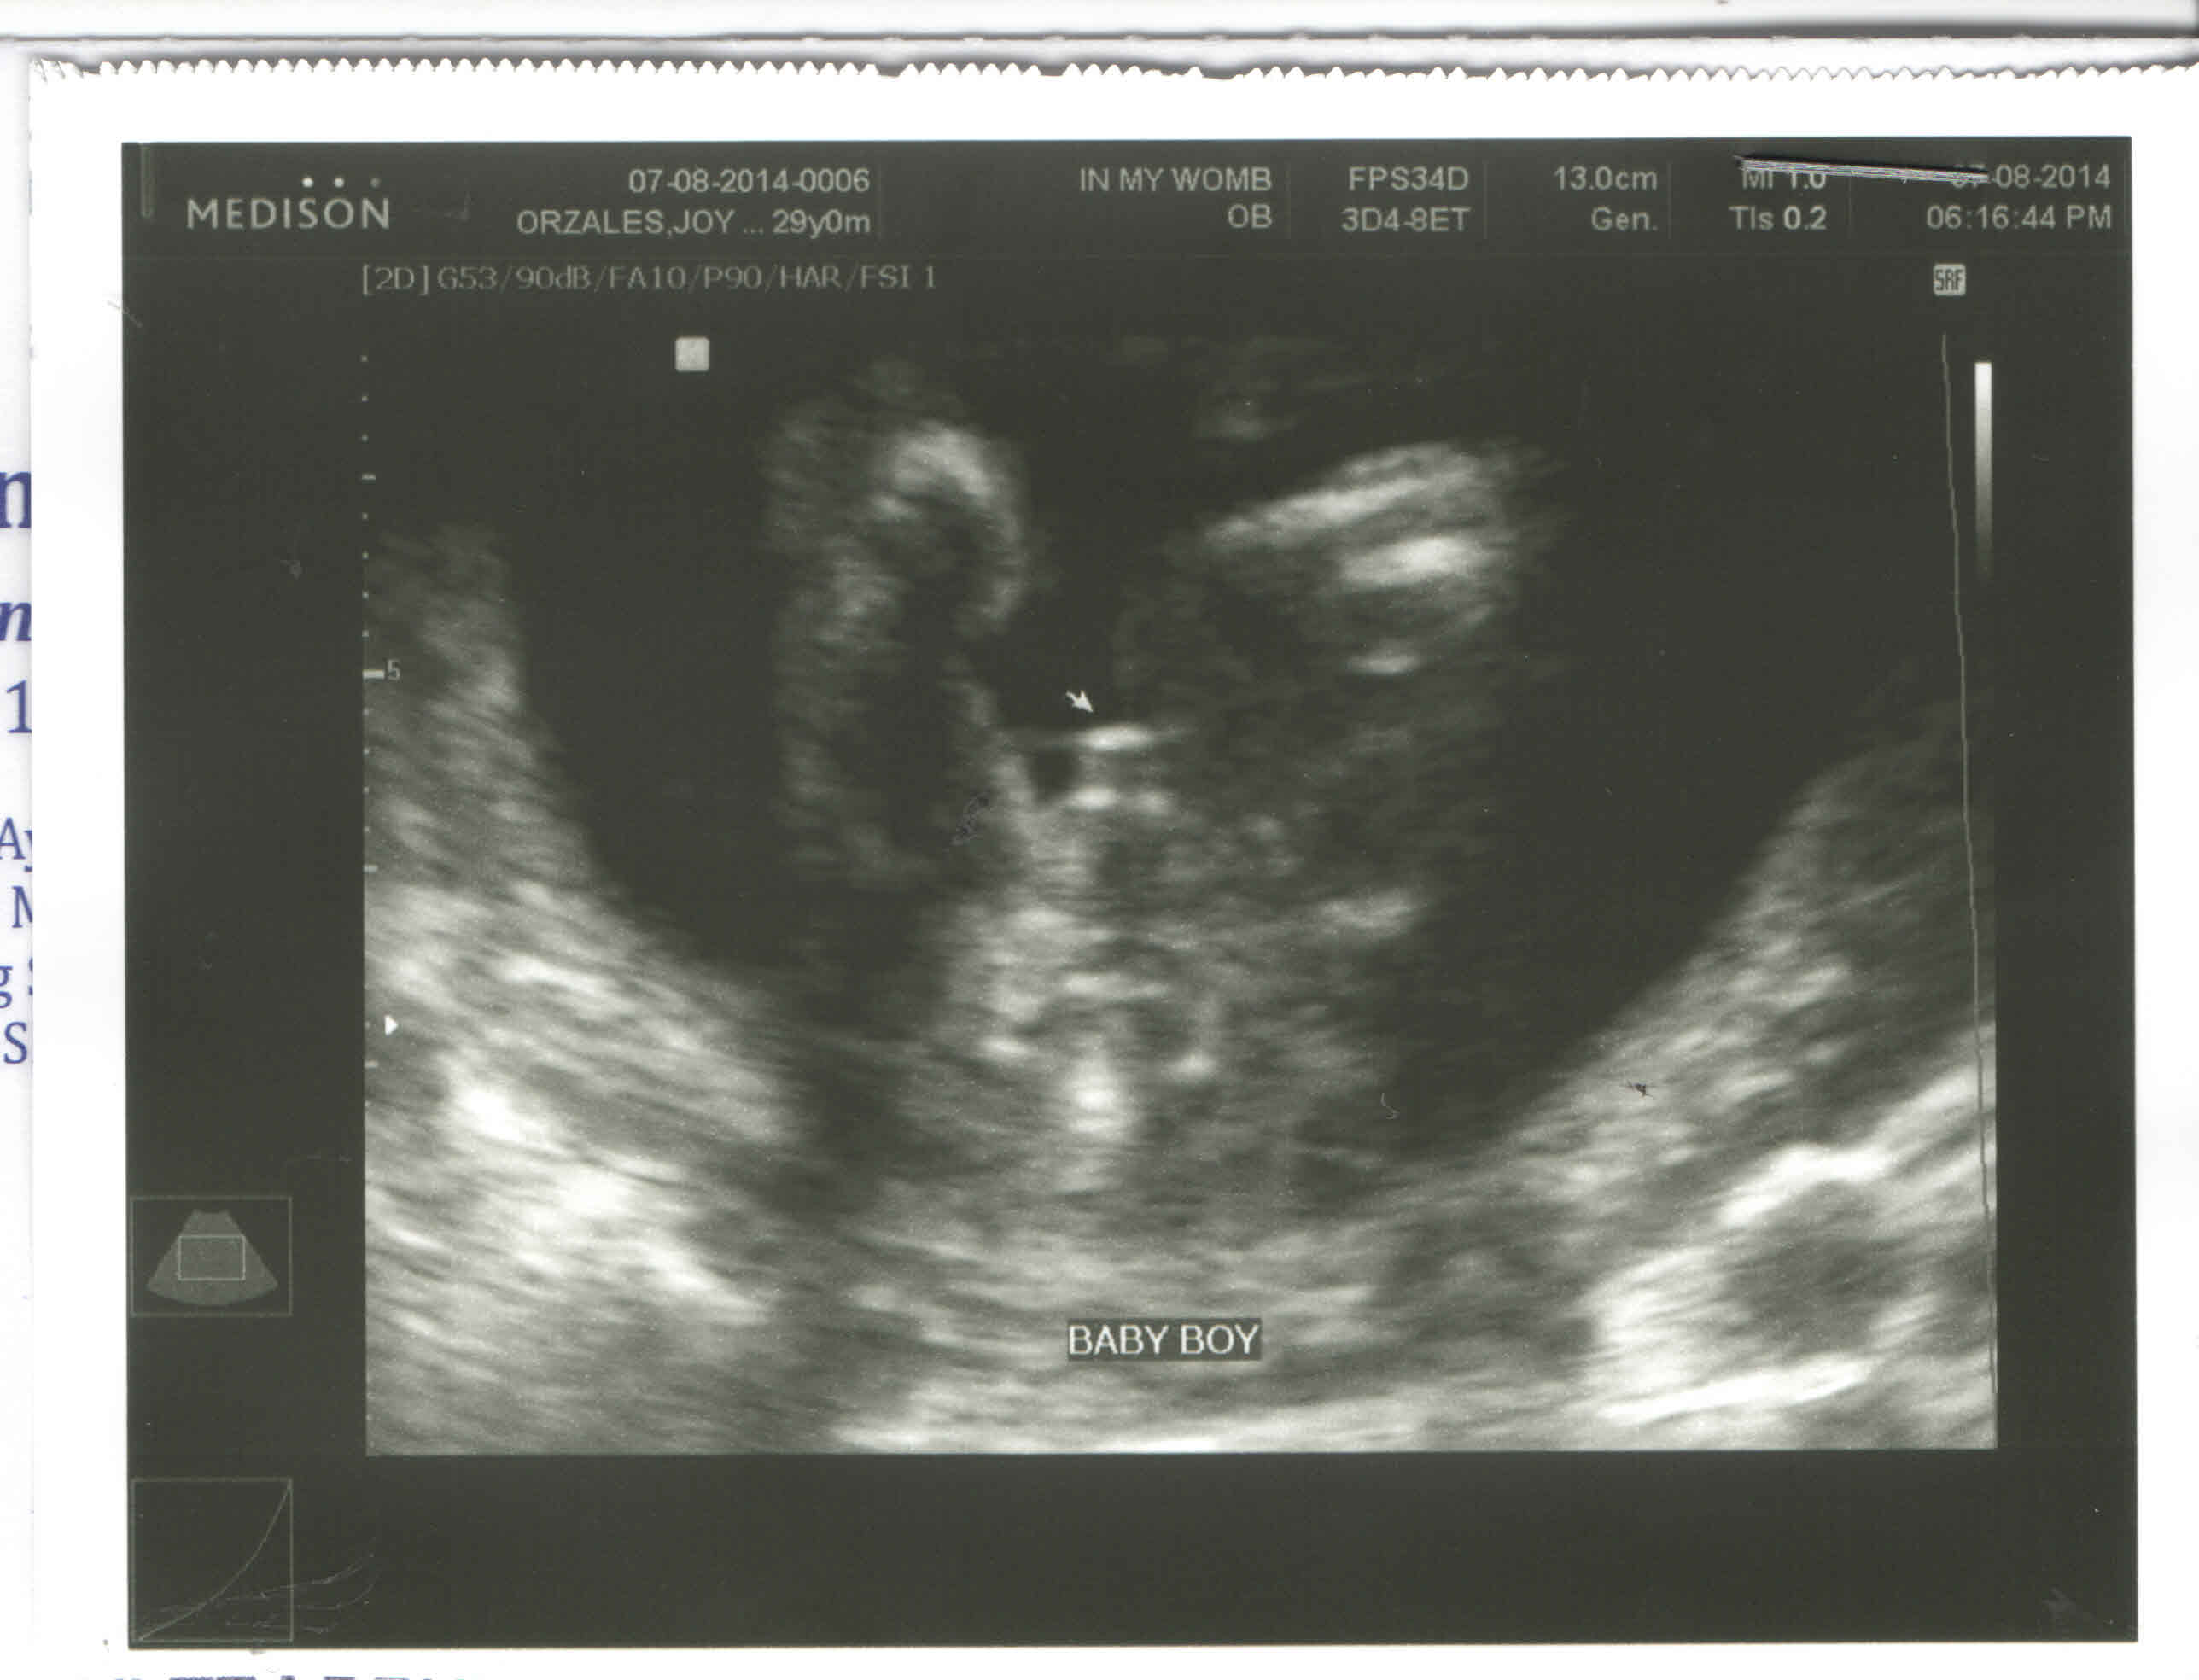

And so, as the scan went by, the doctor asked us if we already know the gender of the baby. We said no. She said, if it’s a boy, we would know even if I was only 16-17 weeks that time. At first, she said she can see a male part but she was not satisfied because it might be the umbilical cord. So she tried so many angles and it was still there. She wanted a good angle so she shook baby a bit and that’s when he opened his legs and the doctor got a good angle. Here’s the scan:

Of course, the daddy was really happy. I have not seen him that happy. I guess it’s really different if you’re a dad and you’re having a son.